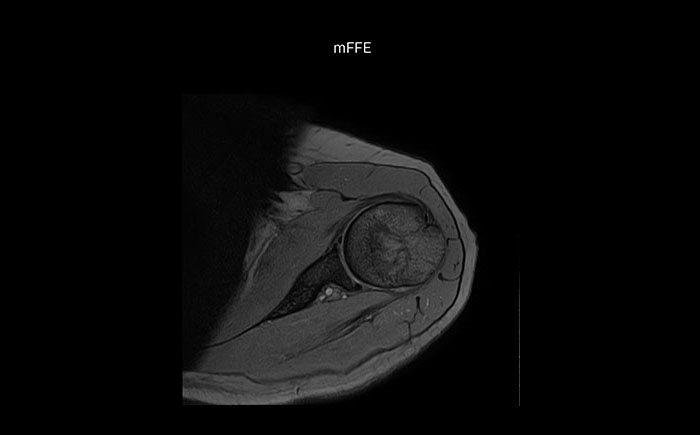

Die Prodiva Schulterspule ist sehr flexibel und hat eine große Abdeckung; dies erleichtert eine gute Positionierung, was wiederum zur ausgezeichneten Bildqualität und hohem SNR beiträgt, die wir in unseren Schulteruntersuchungen erreichen.

Scandauer: 2:55 Minuten, FOV: 160 mm, erfasste Voxel: 0,55 x 0,83 x 3,0 mm.

Scandauer: 04:19 Minuten, FOV: 160 mm, erfasste Voxel: 0,55 x 0,80 x 3,0 mm.

Scandauer: 02:50 Minuten, FOV: 160 mm, erfasste Voxel: 0,70 x 0,99 x 3,0 mm.